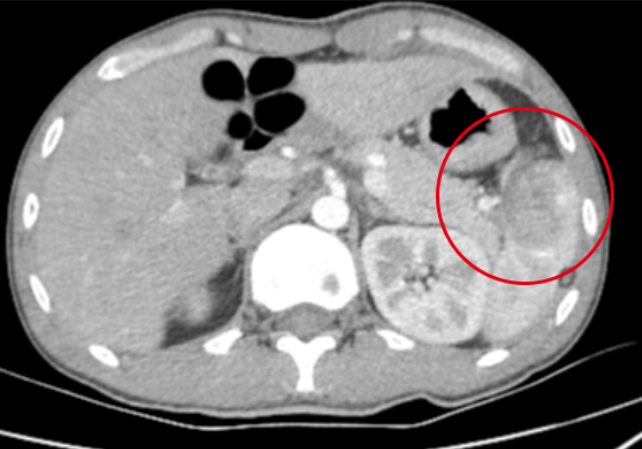

吃飯時(shí)一個(gè)小小的疏忽,可能埋下巨大的健康隱患。誰能想到,一根魚刺竟能“穿越”消化道,最終刺穿乙狀結(jié)腸,引發(fā)急腹癥險(xiǎn)情!近日,我院成功救治了這樣一位特殊患者。這場(chǎng)由魚刺引發(fā)的“腸”險(xiǎn)記,最終在多學(xué)科的高效協(xié)作下化險(xiǎn)為夷。就診經(jīng)過:清晰嚴(yán)謹(jǐn)8月15日,該患者因持續(xù)加重的左下腹脹痛,來到我院消化內(nèi)科就診。接診的張紹珠副主任醫(yī)師詳細(xì)詢問病史并進(jìn)行了仔細(xì)的查體,結(jié)合腹部影像學(xué)結(jié)果,敏銳地判斷出患者存在腸穿孔可能,病情危急!消化內(nèi)科立即發(fā)出會(huì)診邀請(qǐng),外科任培土主任及楊京茹副主任迅速響應(yīng),2025-08-30